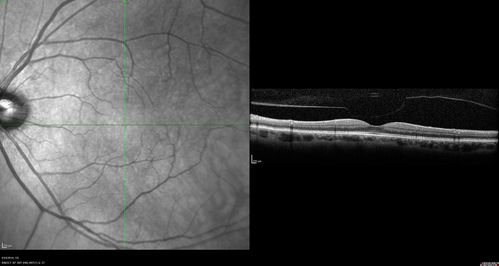

Lung Cancer Metastasis to Right Eye

63 year old female with vision loss for 6 weeks. She had been scheduled for cataract surgery and then a tumor was found. She was ultimately diagnosed with lung cancer. Vision is 20/100

Non Small Cell Lung Cancer - Metastasis to Choroid